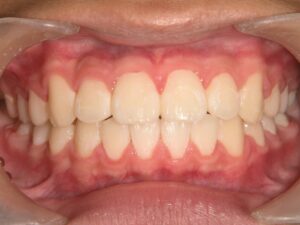

第2期治療終了時

顔貌写真

口腔内写真

治療結果

上下の歯のデコボコが改善

全体的な咬み合わせの緊密化

治療費(調整料含めて)

約95万円(第1期治療…40万円、第2期治療…55万円)

第1期治療期間

第1期治療開始:2021年8月

第1期治療終了:2022年1月

動的治療期間:5か月

第2期治療期間

第2期治療開始:2024年9月

第2期治療終了:2025年7月

動的治療期間:10か月

合計期間

3年10か月(動的治療期間:1年3か月+経過観察期間:2年7か月)

患者様は歯のデコボコを主訴で来院しましたが、第1期治療で歯列拡大+前歯部矯正を行ったことで、第2期治療で非抜歯矯正にて治療終了することができました。